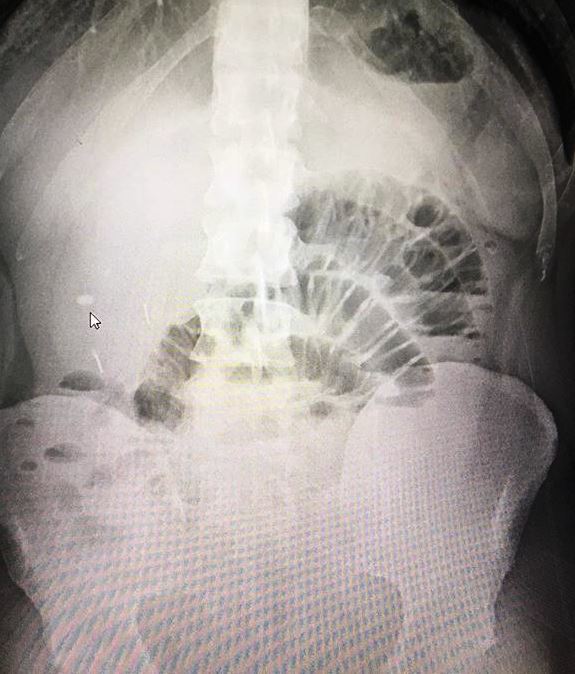

Qual o achado radiográfico que sugere obstrução intestinal em Delgado?

“Empilhamento de moedas”.